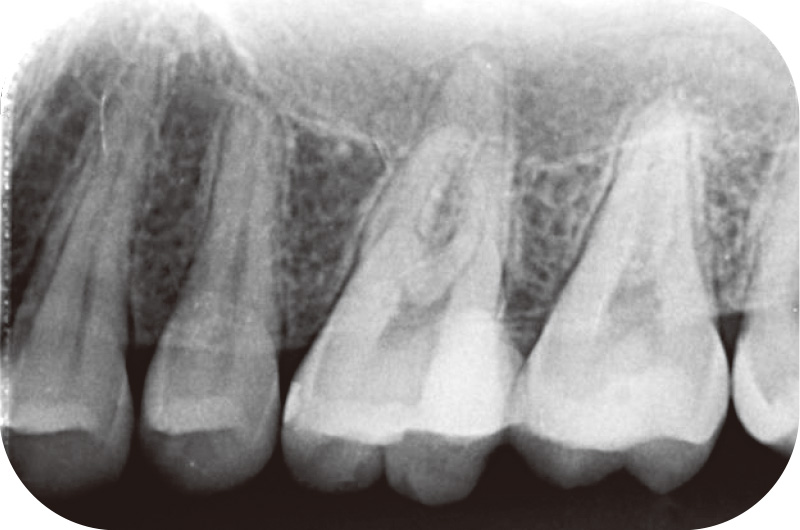

患者は20歳男性、左上臼歯部の違和感を主訴に来院した。26は以前から度々自発痛を呈していたが、しばらくすると落ち着いたため、放置していた。初診時のデンタルX線写真を示す(図3)。26に歯髄に近接する明らかなカリエスを認めた。26の診査結果は軽度の打診痛、EPT(+)、冷温刺激にてやや疼痛を認め、持続時間は30秒程度であったため、歯髄は可逆性歯髄炎、根尖周囲組織は正常と診断し、生活歯髄療法(VPT)を行った。カリエスを丁寧に除去したが、一部露髄が認められたため、直接覆髄を試みた。NaClOにて露髄面の止血を行い、止血確認後にMTAセメントにてVPTを行った。その際、マイクロスコープにて露髄面の出血を確認し、やや血流は悪いと感じたが、若年者の生活歯髄に期待し、歯髄保存を選択した(図4)。その後、しばらくは経過良好であったが、半年後に突然強度の自発痛を自覚し、EPT(-)を示したため、歯髄壊死、症状のある根尖性歯周炎と診断し、感染根管治療に踏み切った。

![[写真] 生活歯髄療法(VPT)後のデンタルX線](/academic/dentalmagazine/wp-content/uploads/sites/2/2025/09/194-17_photo04.jpg)

図4 生活歯髄療法(VPT)後のデンタルX線。MTA併用 -